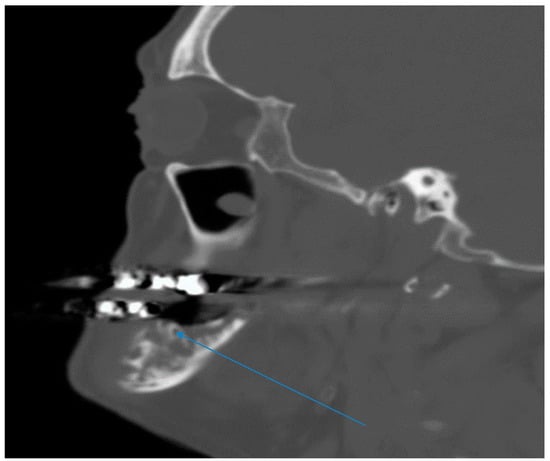

His vital signs were normal. Mouth examination showed exposed bone around the root sites of teeth #18 and 19 (see arrow), with artificial crowns over several teeth in the lower jaw (Figure 1). There were no enlarged cervical lymph nodes and examination of other systems was unremarkable.

Figure 1.

Photograph of the open mouth with arrow pointed at exposed bone around teeth #18 and 19.